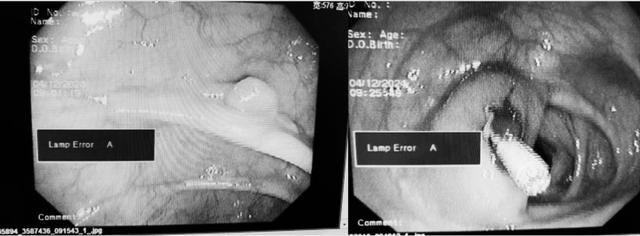

近日,今年70岁的申大爷(化名)一周前出现食欲下降、腹胀等症状,以为是小毛病,吃吃药就好了,结果连吃几天后发现没啥效果,便急忙在家人的陪同下来到了邵东市中医医院脾胃肾病科门诊就诊,医师建议完善肠镜检查,经肠镜检查后发现申大爷升结肠有一枚直径6mm的无蒂息肉。

在完善一系列术前检查后,刘文志医师为申大爷实施内镜下息肉切除术,成功将申大爷肠壁上的肿物完整切除下来,术后使用钛夹封闭创面。整个手术过程顺利,无不适情况。

术后第二天、第二周电话随访,都诉无特殊不适。追踪病检结果提示:(升结肠)管状腺瘤,低级别上皮内瘤变。